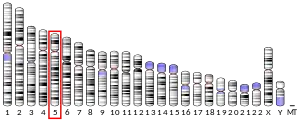

| External IDs | OMIM: 605879 HomoloGene: 23150 GeneCards: KCNN2 | ||||||||||||||||||||||||||||||||||||||||||||||||||